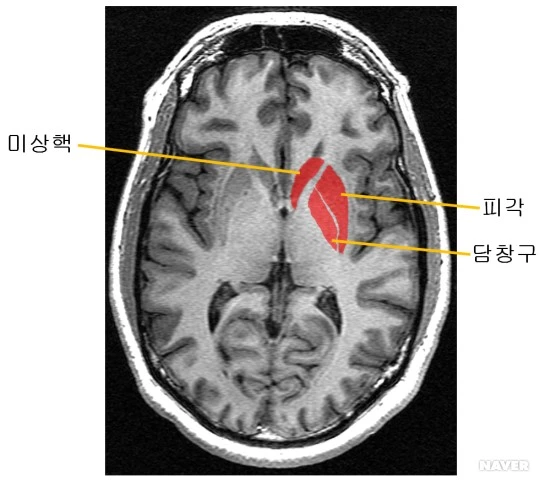

우리 뚝배기를 열어보면 저런 순두부가 차있는데, 저 중 붉은 부분을 통틀어 '선조체'라고 한다. 사람이 받아들이는 여러 종류의 자극을 통합하는 부분이라고 한다. 인간이 행복함을 느껴 '도파민' 호르몬이 분비되면, 선조체의 회로가 빠르게 진동한다. 반면에, 도파민이 없을 때는 활성이 낮아져서 천천히 진동한다.

'도파민' 분비가 많아져 선조체 회로가 빠르게 진동하면 상대적으로 주변 환경이 느린 것처럼 느껴진다. '도파민' 분비가 없어 선조체 회로가 천천히 진동하면 상대적으로 주변 환경이 빠른 것처럼 느낀다.

즉, 재미가 있으면 주변 환경이 느린 것처럼 느끼니(사실은 안 느린데) 시간이 후다닥 가버리는 것이다. 반대로, 재미가 없으면 주변 환경이 빠른 것처럼 느끼니(사실은 안 빠른데) 시간이 오지게 안 가는 것이다. 애꿎은 시계만 자꾸 보는 것이다.

글을 쓸 때, 내 몸에서는 도파민이 나오고 선조체가 활발해진다. 그래서 주변이 느린 것처럼 느끼니 시간이 훅 가버린다. 한 사람의 인생이 이러한 질적인 시간으로 많이 채워져 있을수록 모든 면에서 앞서나가지 않을까 싶다.